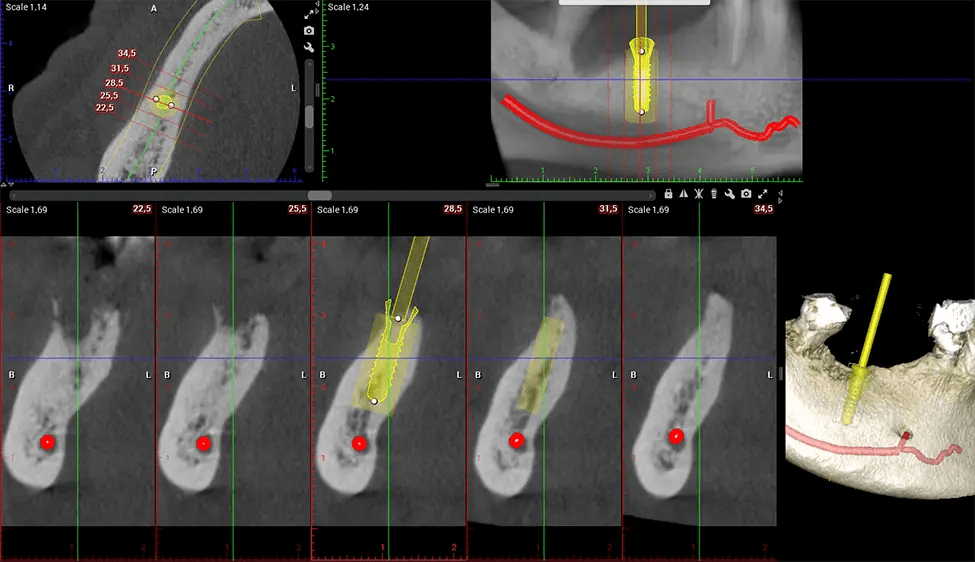

When paired with extractions, dental implant placement, or bone grafting, CBCT technology can provide you with a quicker and much more comfortable experience. This is because the 3D image provides a more detailed picture of your entire oral cavity, allowing your dentist to walk you through each step of the process before it occurs. This often helps patients feel more prepared and comfortable overall, especially if they have had a traumatic experience with past dental treatments.

After the scanning process, the captured X-ray images are processed by the CBCT software, which applies algorithms to reconstruct a detailed 3D image of the scanned area. The software compiles these individual X-ray images and creates a digital 3D representation of the patient’s anatomy. The reconstructed 3D CBCT image can be viewed and analyzed by the dentist or radiologist. This image can be manipulated, rotated, and zoomed in or out to examine specific structures and evaluate the patient’s condition.

Planmeca Viso G7 CBCT ( Cone Beam CT Scan ) is designed to surpass the demands of industry leaders, specialists, and large institutions. It’s has a large ø25×30 cm sensor with four built-in cameras. It can capture unlimited volume sizes from a ø3×3 cm to a ø30x30cm volume capturing the skullcap through C7 on the cervical spine. The Planmeca Viso G7 offers the industry’s largest single volume scan of ø30×19 cm. It’s poised to handle advanced imaging modalities such as Planmeca ProFace® and Planmeca 4D™ Jaw Motion technology. The occipital head support allows an unimpeded view of facial tissue.

Planmeca is the only manufacturer clinically proven to dramatically reduce patient radiation without sacrificing image quality. Planmeca Ultra Low Dose™ achieves an average reduction in dose of 77% without a statistical reduction in image quality allowing doctors to incorporate 3D imaging into routine protocols with effective patient radiation often lower than 2D intraoral imaging. This increases patient care, allows doctors to diagnose more dentistry, and often earlier in disease progression, than with 2D imaging alone.

Planmeca 3D units also include the industry’s only patient motion detection and correction technology, Planmeca CALM™. This technology corrects movement during CBCT acquisition reducing the risk of retakes.